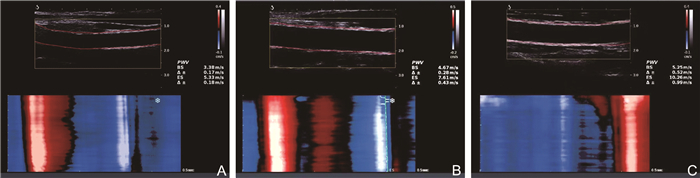

目的 应用极速脉搏波技术评估不同活动度系统性红斑狼疮(SLE)患者的血管弹性并探究其相关危险因素。 方法 选取2020年10月—2024年4月就诊于蚌埠医科大学第一附属医院的116例SLE患者,根据SLE疾病活动性指数2000分为轻度活动组(57例)和中重度活动组(59例),纳入45名健康成年人作为对照组。测量各组的颈动脉内中膜厚度(IMT)、收缩期起始时的脉搏波传导速度(PWV-BS)及收缩期末的脉搏波传导速度(PWV-ES),比较3组颈动脉参数及临床资料,分析脉搏波传导速度(PWV)与各指标之间的相关性。 结果 3组间PWV-BS、PWV-ES比较,中重度活动组>轻度活动组>对照组(P<0.05)。PWV-BS与颈总动脉IMT(r=0.315, P < 0.001)、收缩压(r=0.190, P=0.041)、舒张压(r=0.191, P=0.040)呈正相关关系,PWV-ES与颈动脉分叉处IMT(r=0.274, P=0.003)、颈总动脉IMT(r=0.361, P < 0.001)、舒张压(r=0.252, P=0.006)呈正相关关系。 结论 SLE患者的颈动脉弹性减低明显早于健康者,极速脉搏波可定量评估SLE患者颈动脉弹性,且不受限于时期,这为临床早期动脉硬化评估提供了客观依据。 Abstract:Objective To make an assessment of vascular elasticity in patients with systemic lupus erythematosus (SLE) at varying levels of disease activity using ultrafast pulse wave technique, and to investigate associated clinical risk factors. Methods A total of 116 SLE patients admitted to the First Affiliated Hospital of Bengbu Medical University from October 2020 to April 2024 were selected. Patients were divided into a mild activity group (n=57) and a moderate-to-severe activity group (n=59) according to SLE disease activity index 2000. Additionally, 45 healthy adults were included as the control group. Carotid intima-media thickness (IMT), pulse wave velocity at the beginning of systole (PWV-BS), and pulse wave velocity at the end of systole (PWV-ES) were measured in each group. Clinical data of each group were recorded and analyzed. Carotid artery parameters and clinical data of the three groups were compared to analyze the correlation between PWV parameters and various indicators. Results Both PWV-BS and PWV-ES showed significant differences among the three groups, following the pattern: moderate-to-severe activity group > light activity group > control group (P < 0.05). PWV-BS was positively correlated with common carotid artery IMT (r=0.315, P < 0.001), systolic blood pressure (r=0.190, P=0.041), and diastolic blood pressure (r=0.191, P=0.040). PWV-ES was positively correlated with carotid bifurcation IMT (r=0.274, P=0.003), common carotid artery IMT (r=0.361, P < 0.001), and diastolic blood pressure (r=0.252, P=0.006). Conclusion The reduction in carotid artery elasticity in SLE patients occurs significantly earlier compared to healthy individuals. Ultrafast pulse wave is valuable, time-independent, and objective tool for quantitative assessing early vascular changes in patients with SLE, thus facilitating the early detection and clinical management of atherosclerosis. -

组别 例数 分叉处IMT(mm) 颈总动脉IMT(mm) PWV-BS(m/s) PWV-ES(m/s) 对照组 45 0.71(0.69, 0.74) 0.65(0.60, 0.69) 4.48(4.02, 4.96) 5.75(5.34, 6.29) 轻度活动组 57 0.75(0.71, 0.80)a 0.69(0.63, 0.74)a 5.22(4.75, 5.68)a 6.85(6.46, 7.66)a 中重度活动组 59 0.79(0.73, 0.85)a 0.71(0.68, 0.76)ab 6.00(5.37, 6.55)ab 7.91(7.28, 8.73)ab H值 22.400 37.215 73.939 81.189 P值 < 0.001 < 0.001 < 0.001 < 0.001 注:与对照组比较,aP < 0.05;与轻度组比较,bP < 0.05。 -